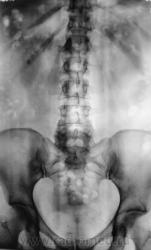

После введения контрастного вещества урограммы произведены на 7 и 15 минутах.

В проекции среднего сегмента правой почки тень конкремента. Отсутствие признаков расширения собрательной системы правой почки.

т.е на фоне контраста тени не видно?

Да, контраст "покрыл" тень рентгеноположительного конкремента.